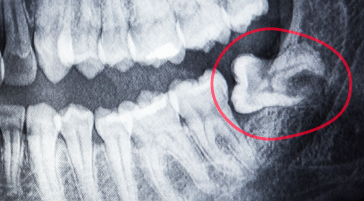

Extração de Siso

Realizada com técnica segura para aliviar dores, prevenir inflamações e proteger sua saúde bucal.

Dentes Inclusos

Remoção com precisão para evitar infecções, cistos e desconfortos futuros.